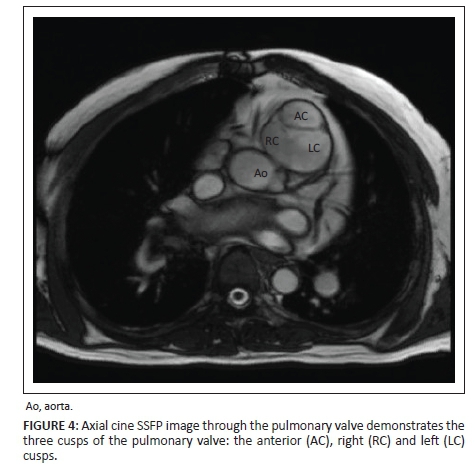

The pulmonary artery is the most anterior great vessel on the axial images. The pulmonary valve appears anatomically very similar to the aortic valve and also has three cusps: the anterior, left and right cusps (Figure 4).